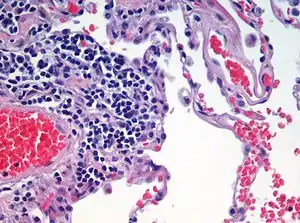

| Advanced centrilobular emphysema showing total lobule involvement on the left side | |

A sign of emphysema in smokers is the finding of a higher number of alveolar macrophages sampled from the bronchoalveolar lavage (BAL) in the lungs. The number can be four to six times greater in those who smoke than in non-smokers.[23]

Centrilobular

Centrilobular emphysema, also called centriacinar emphysema, affects the centre of a pulmonary lobule (centrilobular) in the lung, the area around the terminal bronchiole and the first respiratory bronchiole, and can be seen on imaging as an area around the tip of the visible pulmonary artery. Centrilobular emphysema is the most common type usually associated with smoking, and with chronic bronchitis.[17] The disease progresses from the centrilobular portion, leaving the lung parenchyma in the surrounding (perilobular) region preserved.[24] Usually the upper lobes of the lungs are affected.[17]